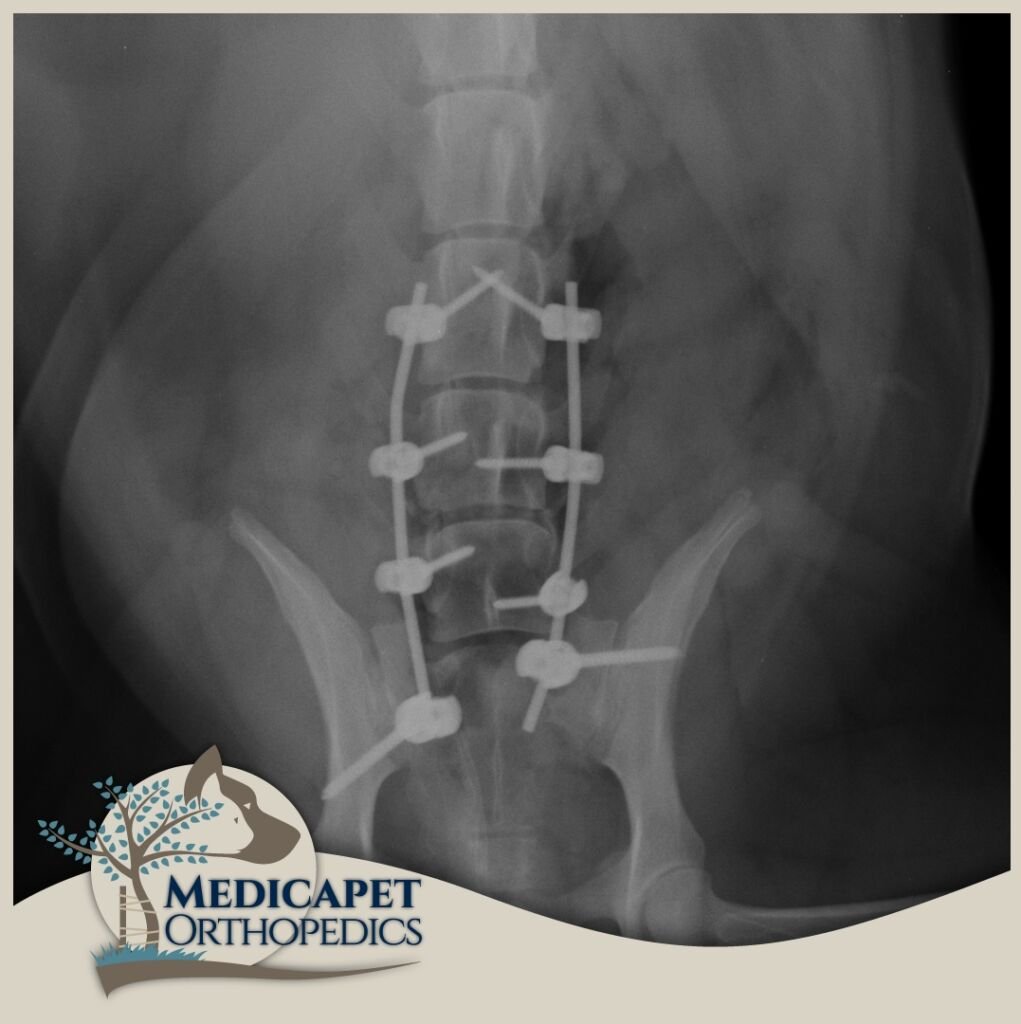

Kemik dokulara paralel seyreden ya da onların içinde bulunan sinir yapıları, kemik hasarlarıyla birlikte zarar görebilir. Yumuşak yapılı sinir dokuları en küçük travmaya karşı hassastır ve korunmaya ihtiyaç duyar. Beyin ve omurilik gibi organlar kafatası ve omurga tarafından korunur, bu nedenle kemik dokuların tedavi ve onarımı sinir dokusuna zarar vermeden yapılmalıdır. Ayrıca bazı sinir hastalıklarında da (örneğin tümörler) kemik dokuya müdahale gerekebilir. Bu yüzden nöroloji ve ortopedi yakından ilişkilidir.

Sinir sistemi; Merkezi Sinir Sistemi (beyin, beyincik, beyin sapı, omurilik) ve Periferik Sinir Sisteminden (gangliyonlar, sinirler, sinir uçları) oluşur. Kliniğe başvuran hastaların çoğunda trafik kazaları, düşme, saldırılar gibi nedenlerle omurga kırıkları, kafatası travmaları veya felç durumları görülmektedir. Bazı ırklarda genetik yatkınlık da omurga sorunlarına yol açabilir.

Nörolojik cerrahide operasyon kadar öncesi ve sonrası bakım da önemlidir. Operasyon sonrası ödem sinir dokularda bası oluşturabileceğinden dikkatli cerrahi, uygun ilaç tedavisi ve gerektiğinde fizik tedavi süreci titizlikle uygulanmalıdır. Sinir dokusu diğer dokulara göre çok daha yavaş iyileşir; küçük bir kesik deride kısa sürede düzelirken omurilikte kalıcı felce yol açabilir.